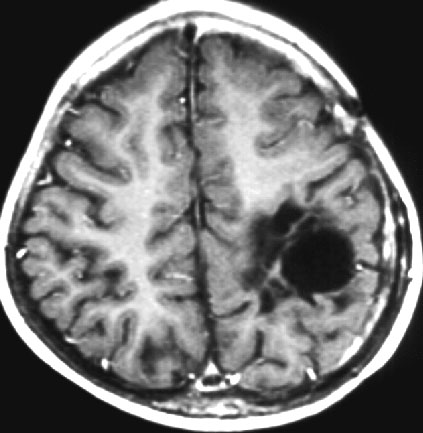

2歳の子どもの例

2歳の時に右の片麻痺と意識障害で発症しました。手術できれいにとれて,20年経ちますが再発はありませんし,運動麻痺もありません。この画像を見ると左の一次運動野が侵されていて,麻痺が治るということは信じられないのですが,2歳以下の小さな子どもの麻痺は治ることがあります。乳幼児のこの腫瘍は積極的な摘出を行った方がいいでしょう。

- 大脳の表面にできて,とても大きな腫瘍で,大きなのう胞(液体がたまる)を伴います

- 液体のたまっているのう胞が大部分です

- 不正形に造影剤で増強されて白く映る塊が見えますが,それが本体です